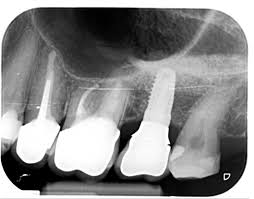

Wurzelkanalbehandlung Nach Bereits Erfolgter Wurzelspitzenresektion Zwp Online Das Nachrichtenportal Fur Die Dentalbranche